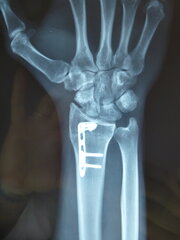

Η αντιμετώπιση της ψευδάρθρωσης του σκαφοειδούς είναι πάντοτε χειρουργική. Με ραχιαία ή παλαμιαία προσπέλαση – αναλόγως της μορφολογίας της ψευδάρθρωσης – προσπελάζεται η εστία του κατάγματος, καθαρίζεται, αποκαθίσταται ο άξονας του σκαφοειδούς και σταθεροποιείται το σκαφοειδές με ειδική βίδα ή βελόνες, με παράλληλη τοποθέτηση οστικών μοσχευμάτων. Μπορεί επιπλέον να προστεθεί και οστεοτομία κλειστής σφήνας του περιφερικού άκρου της κερκίδος. Στις περιπτώσεις άσηπτης νέκρωσης το μόσχευμα πρέπει να είναι αγγειούμενο – για να προσδώσει αιμάτωση στο νεκρωμένο κεντρικό τμήμα – και λαμβάνεται με μικροχειρουργικές τεχνικές από το περιφερικό τμήμα της κερκίδος.

<p>Μετεγχειρητικά 1</p>

Μετεγχειρητικά 1

<p>Μετεγχειρητικά 2</p>

Μετεγχειρητικά 2